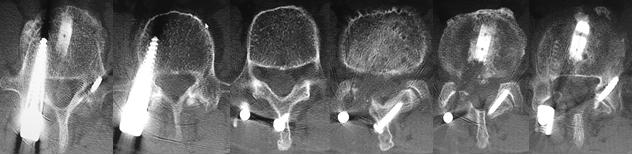

2,术后1周:UPS螺钉位置佳均在椎弓根内;TFS完美穿越棘突、椎板、关节突、椎弓根。

螺钉完美